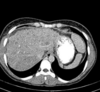

Na TC a avaliação é feita na fase pré-contraste. Avalia-se objetivamente através do valor absoluto e comparativo do ROI (diferença >5 entre fígado e baço) e subjetivamente através da visualização dos vasos.

Verdadeiro.